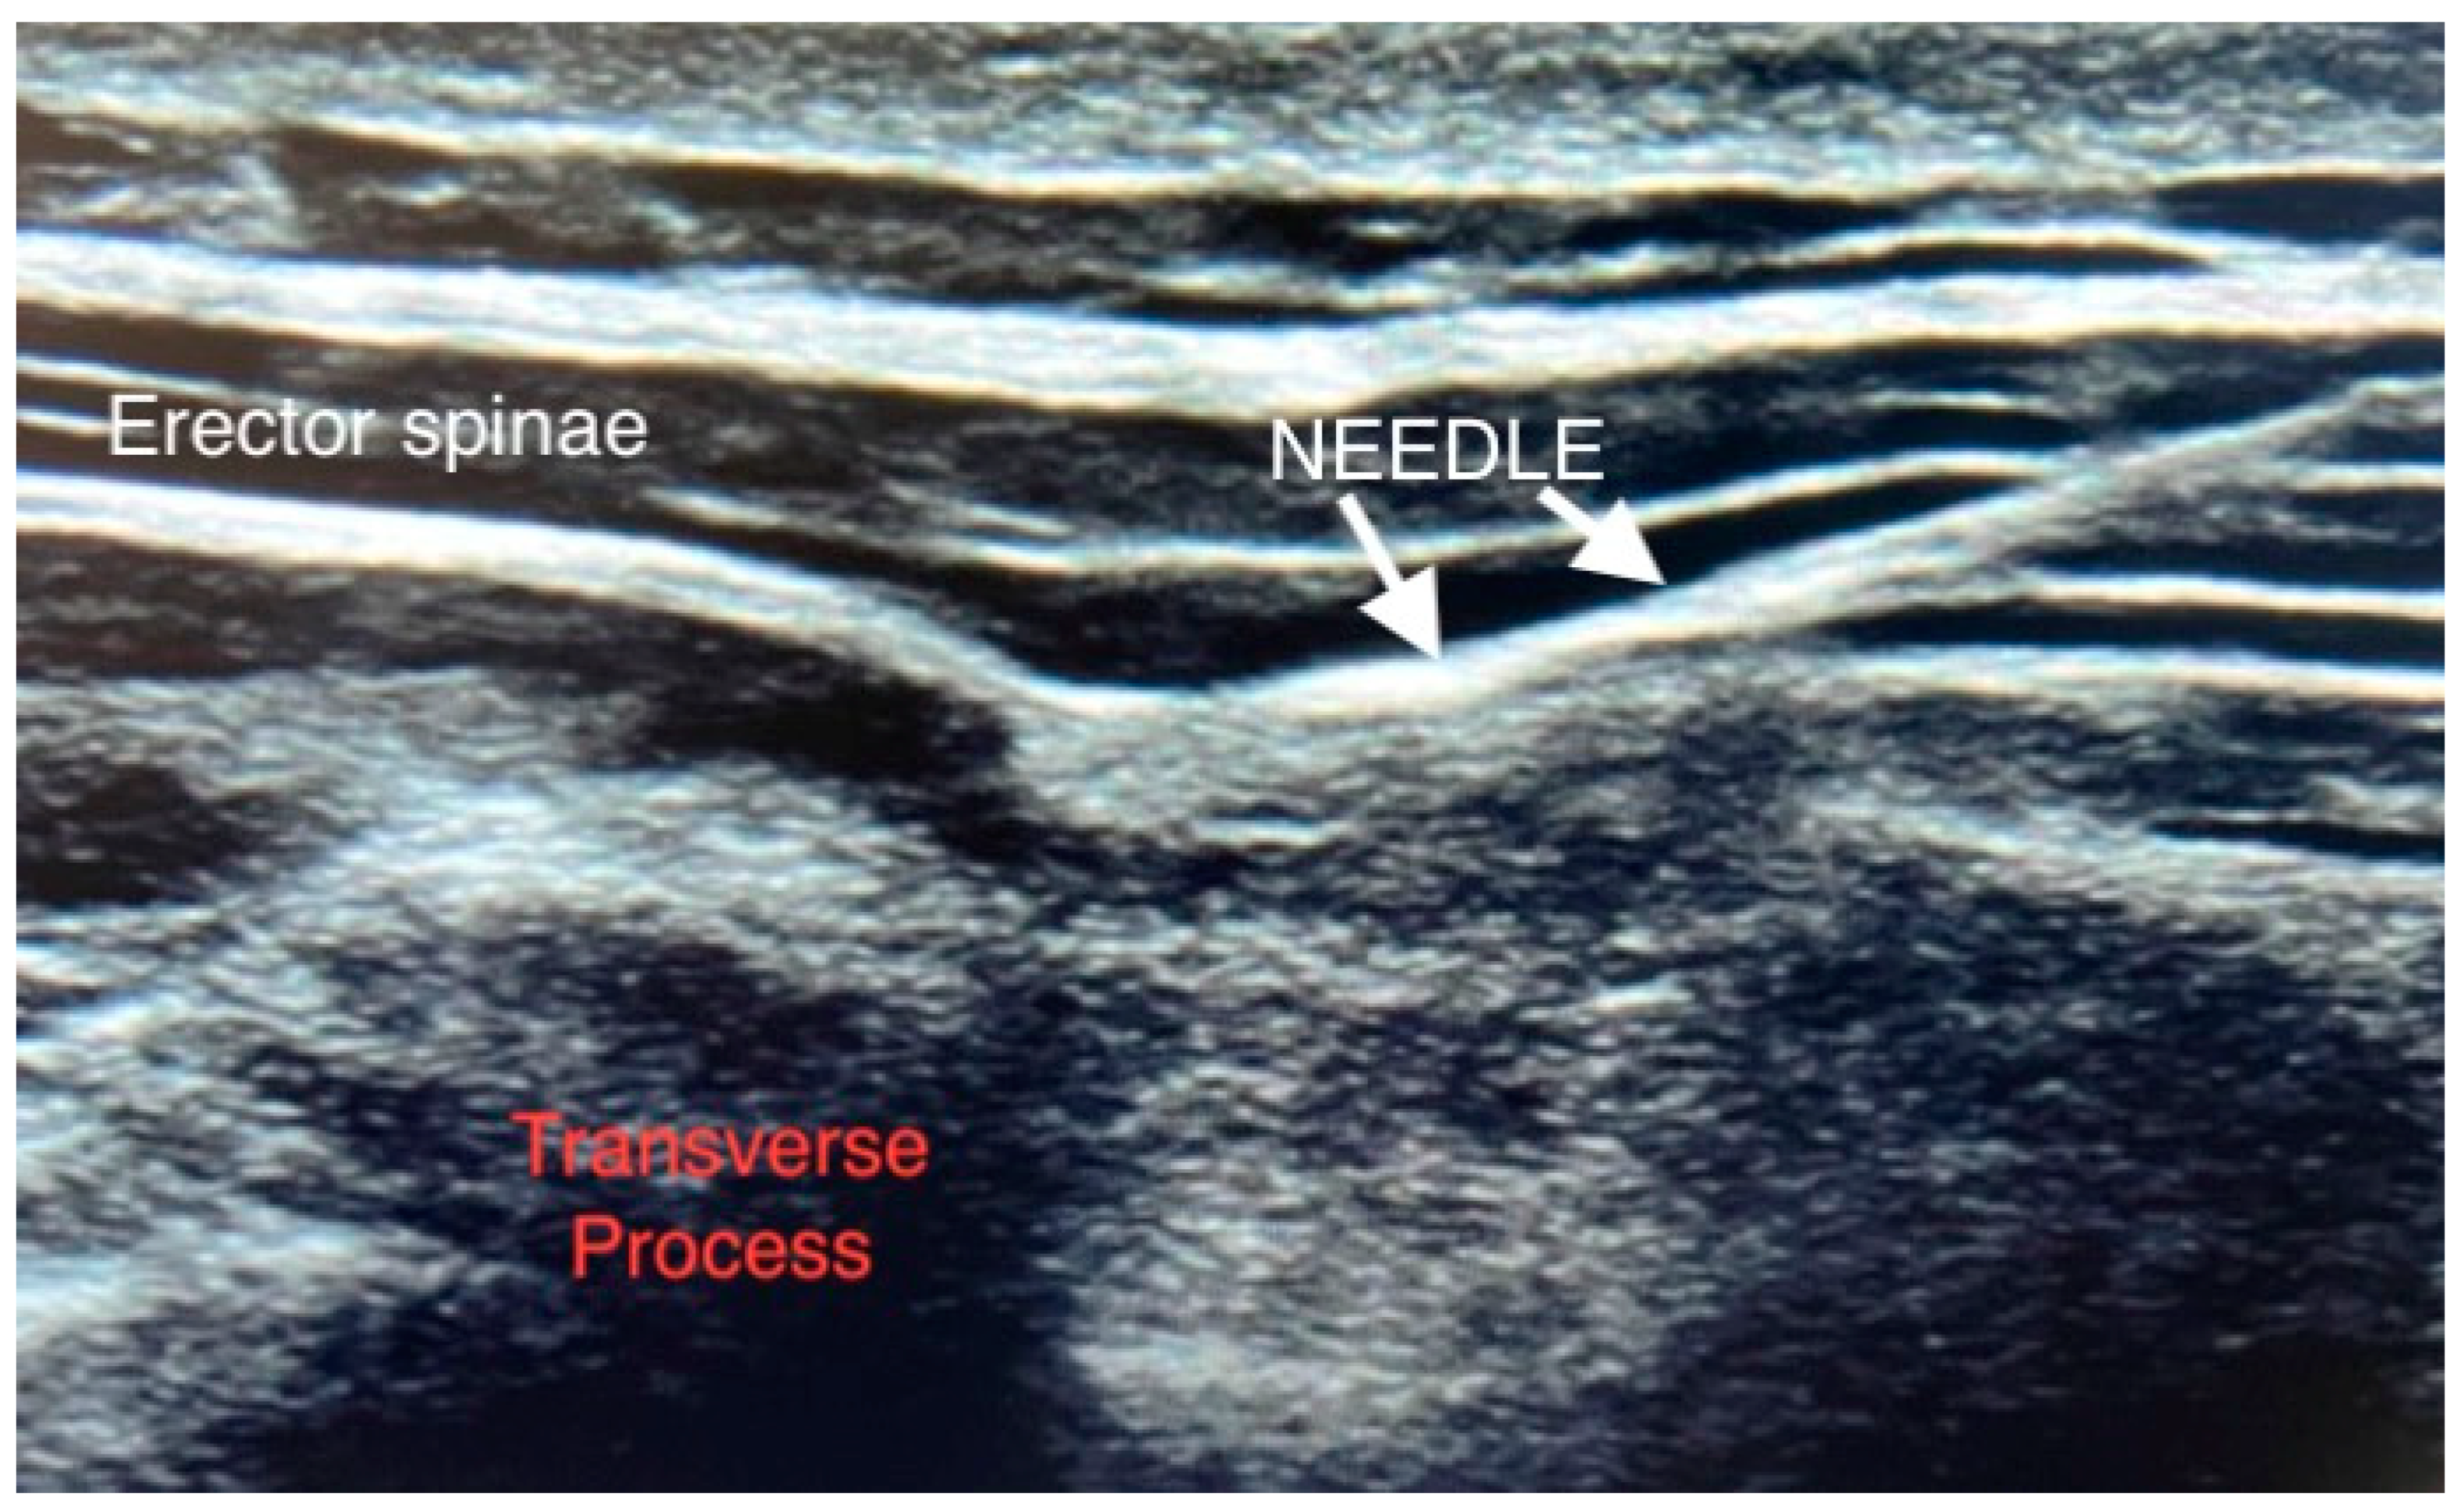

2. Patients and Method